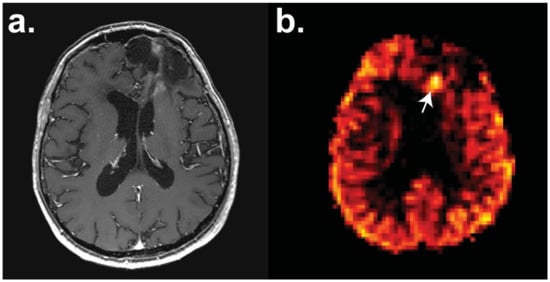

- Ozsunar, Y.; Mullins, M.E.; Kwong, K.; Hochberg, F.H.; Ament, C.; Schaefer, P.W.; Gonzalez, R.G.; Lev, M.H. Glioma recurrence versus radiation necrosis? A pilot comparison of arterial spin-labeled, dynamic susceptibility contrast enhanced MRI, and FDG-PET imaging. Acad. Radiol. 2010, 17, 282–290. [Google Scholar] [CrossRef]

- Ye, J.; Bhagat, S.K.; Li, H.; Luo, X.; Wang, B.; Liu, L.; Yang, G. Differentiation between recurrent gliomas and radiation necrosis using arterial spin labeling perfusion imaging. Exp. Ther. Med. 2016, 11, 2432–2436. [Google Scholar] [CrossRef]

- Razek, A.; El-Serougy, L.; Abdelsalam, M.; Gaballa, G.; Talaat, M. Differentiation of residual/recurrent gliomas from postradiation necrosis with arterial spin labeling and diffusion tensor magnetic resonance imaging-derived metrics. Neuroradiology 2018, 60, 169–177. [Google Scholar] [CrossRef]

- Nyberg, E.; Honce, J.; Kleinschmidt-DeMasters, B.K.; Shukri, B.; Kreidler, S.; Nagae, L. Arterial spin labeling: Pathologically proven superiority over conventional MRI for detection of high-grade glioma progression after treatment. Neuroradiol. J. 2016, 29, 377–383. [Google Scholar] [CrossRef] [PubMed]